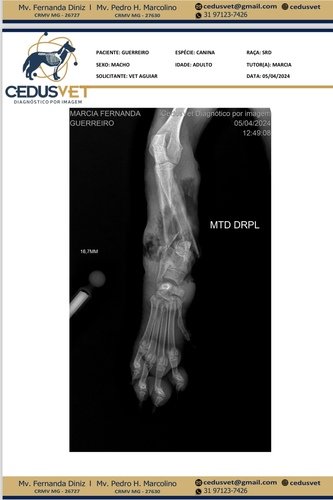

Meu nome é Márcia Lana e acolho o Guerreiro quando ele chegou na minha casa bastante machucado, imediatamente levei-o a clínica veterinária para os primeiros cuidados, Guerreiro estava com febre e gemendo de dor. Ele foi atendido, recebeu as medicações necessárias e fez o raio X, essa primeira parte já foi paga R$680,00 conforme imagem abaixo.

Agora precisamos prosseguir com o tratamento, vai ser necessário amputar a perninha devido a gravidade do ferimento.